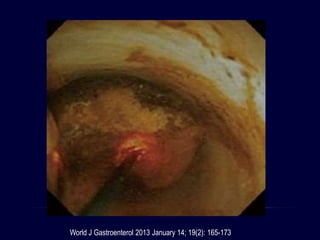

World J Gastroenterol 2013 January 14; 19(2): 165-173

LITOTRIPSIA MECÁNICA

Canastilla electiva a través del endoscopio

Dispositivo de emergencia para canastillas

impactadas